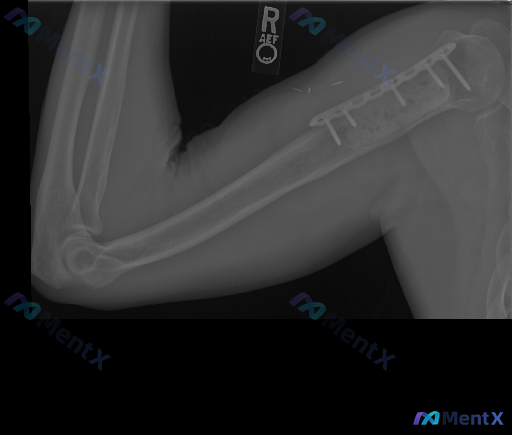

右肱骨近端术后X光:骨密度增高是正常愈合还是预警信号?

整理到一张右肱骨近端术后的侧位X光资料,先把影像里的客观发现列出来:

- 肱骨近端有金属接骨板+多枚螺钉,位置在位;

- 接骨板下方的骨组织区域骨密度增高、结构模糊;

- 肱骨干及远端骨皮质连续,未见明确急性骨折线;

- 肘关节对位正常,无明显脂肪垫征;

- 软组织里有微小的金属密度影(考虑缝合线残留或微粒);

- 没有看到明显的溶骨性/成骨性破坏病灶。

这份资料里的分析提到,这个“骨密度增高+结构模糊”既可能是正常骨痂,也可能是应力遮挡、微动甚至低毒感染的早期表现——同影异病的点很有意思。